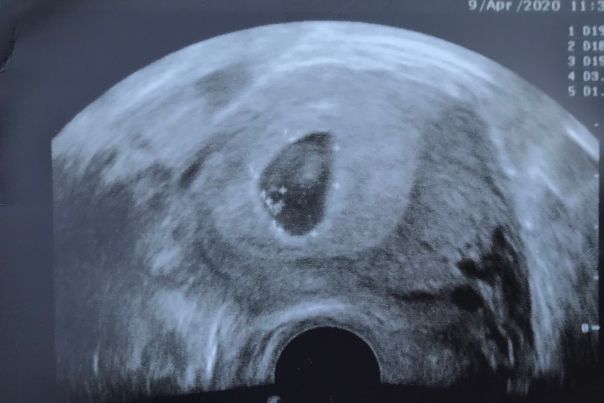

У меня девочка, вот вагинальное узи Изображение